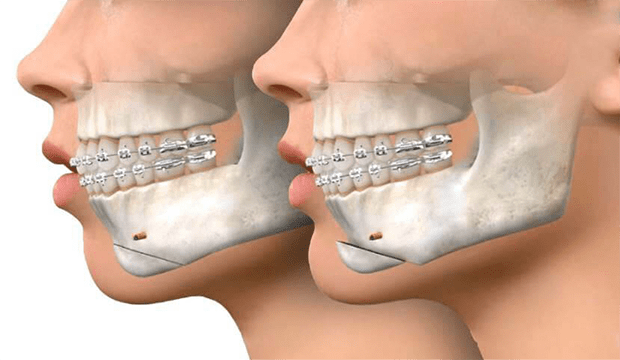

Çoğu durumda, ortodonti uzmanı ameliyattan önce dişlerinize diş teli yerleştirir. Diş telleri genellikle ameliyattan 9 ila 18 ay süre ile dişlerinizi ameliyata hazırlarken, dişlerinizi seviyelendirmeyi ve hizalamayı sağlar.

Ortodontist ve çene cerrahı, tedavi planını geliştirmek için birlikte çalışır. Dişlerin ve çenelerin röntgenleri, resimleri ve modelleri, bu ameliyatın planlamasının bir parçasıdır. Bazen oklüzyonün (alt- üst dişler arasındaki kapanış) tam sağlanamadığı durumlarda ,ilgili dişlerde selektif mölleme ( aşındırma ) yada kaplama tedavisi uygulana bilinir.

Çene cerrahı, çene kemiklerinde kesiler (osteotomi) yaparak çeneleri doğru pozisyona getirir. Çene hareketiniz tamamlandıktan sonra, kemikleri yeni (planlanan) konumlarına sabitlemek için kemik plakaları, vidalar, teller ve lastik bantlar kullanılır. Diş teli için kullanılan bir braketten daha küçük olan bu vidalar zamanla kemik yapısına entegre (kaynaşma) olurlar.

İlk çene iyileşmesi tipik olarak ameliyattan yaklaşık altı hafta sonra sürer, ancak tam iyileşme 12 haftaya kadar sürebilir. Bu sürede ortodontist dişlerinizi diş telleriyle hizalamayı bitirir. Ameliyat ve diş teli dahil olmak üzere tüm ortodontik süreç birkaç yıl sürebilir. Braketler çıkarıldıktan sonra dişin pozisyonunu korumak için tutucular (retainer) kullanılabilir.